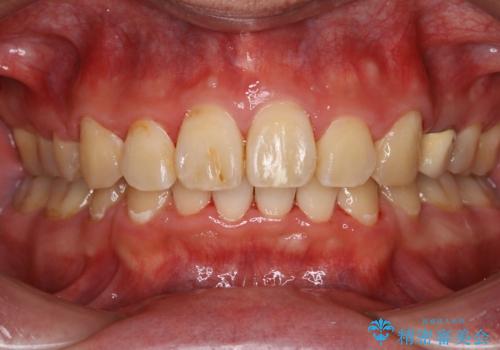

- 上顎前歯の突出感と下顎前歯のガタつきが主訴で来院されました。

出っ歯とガタつきの改善を行うには抜歯が必要と診断し、上下左右第一小臼歯を抜歯する計画を立てました。

ワイヤー治療では歯の傾きを抑えながら大きい距離の移動が可能で、かみ合わせが深くなるリスクも少ないです。